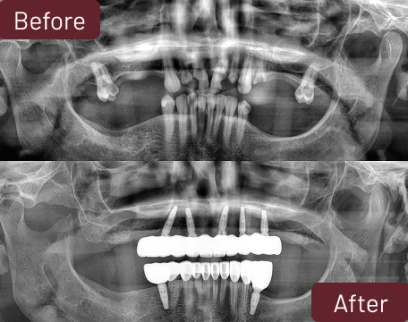

One of the most important steps in Barbie’s journey was finally receiving a clear diagnosis. Through detailed imaging and a complete oral evaluation, the dental team at Forever Clinic identified the full extent of the problem.

Barbie underwent a full mouth implant treatment, restoring both the upper and lower arches. Her dental procedure included:

- Tooth Extractions

- Bone Graft

- Reabsorbable Membrane

- Dental Implants (Top & Bottom)

- Zirconia Prettau Superstructure

- Zirconia Dental Crowns

- Titanium Abutments

- Root Canal Treatment

- Panoramic X-Ray & Oral Evaluation

- Final Check-Ups

These advanced procedures are typically performed with the planning and precision associated with implant specialists and maxillofacial-level care. Every step is designed to ensure stability, comfort, and long-term success.